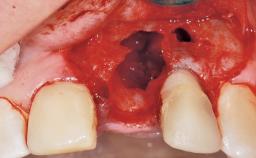

A 33-year-old female patient presented with an upper left central incisor that required extraction after a failed endodontic therapy. The tooth had been traumatized when the patient was a teenager and had undergone several endodontic treatments, including two apicectomy procedures. The patient was in good health and did not smoke. Clinical examination showed that the patient had a high lip line. In full smile, the gingival margins of the upper teeth were visible to the first molars. The gingival margins of central incisors 11 and 21 were only just showing. Examination of tooth 21 confirmed that the tooth was mobile and had hypererupted by 1 mm.

Bone Augmentation Horizontal|Simultaneous

Augmentation Materials Xenogenous|Membrane

Soft Tissue Grafting Simultaneous

Socket Integrity Damage to one or more bone walls

Bone Volume Damage to one or more socket walls